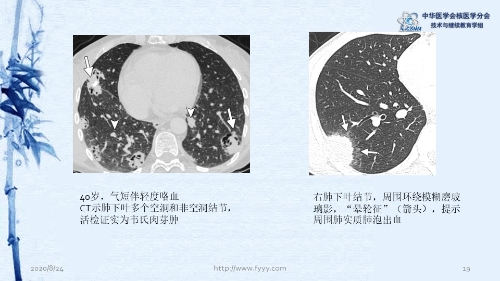

病例82:肉芽肿性血管炎PET-CT显像一例-【CSNM继教学组】郑山 福建医科大学附属第一医院